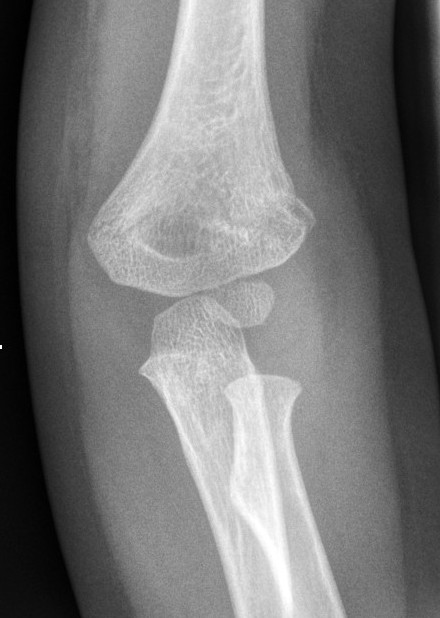

6. Look for obvious fracture lines on the AP view

|

Supracondylar fracture evident on the AP view |